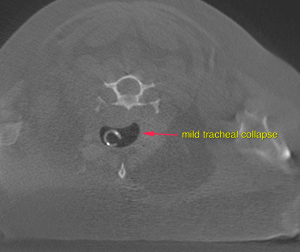

A well-defined, ovoid mass lesion with lobulated appearance and undulating surface is seen in the area of the right parotid salivary gland, measuring 3.8 x 3 x 3.5 cm in size. After contrast administration the mass lesion presents moderate irregular contrast enhancement with multiple spherical non-contrast enhancing areas. The right superficial cervical lymph node is prominent and presents a moderate increased short-to-long-axis ratio of 0.5. The right thyroid gland presents severe enlargement at 2.4 x 2.4 x 2.8 cm. The regular parenchyma is completely displaced by ill-defined moderately contrast enhancing tissue with multiple spherical non-contrast enhancing areas. At the level of the neck the tracheal rings are mildly flattened and the luminal diameter is reduced.